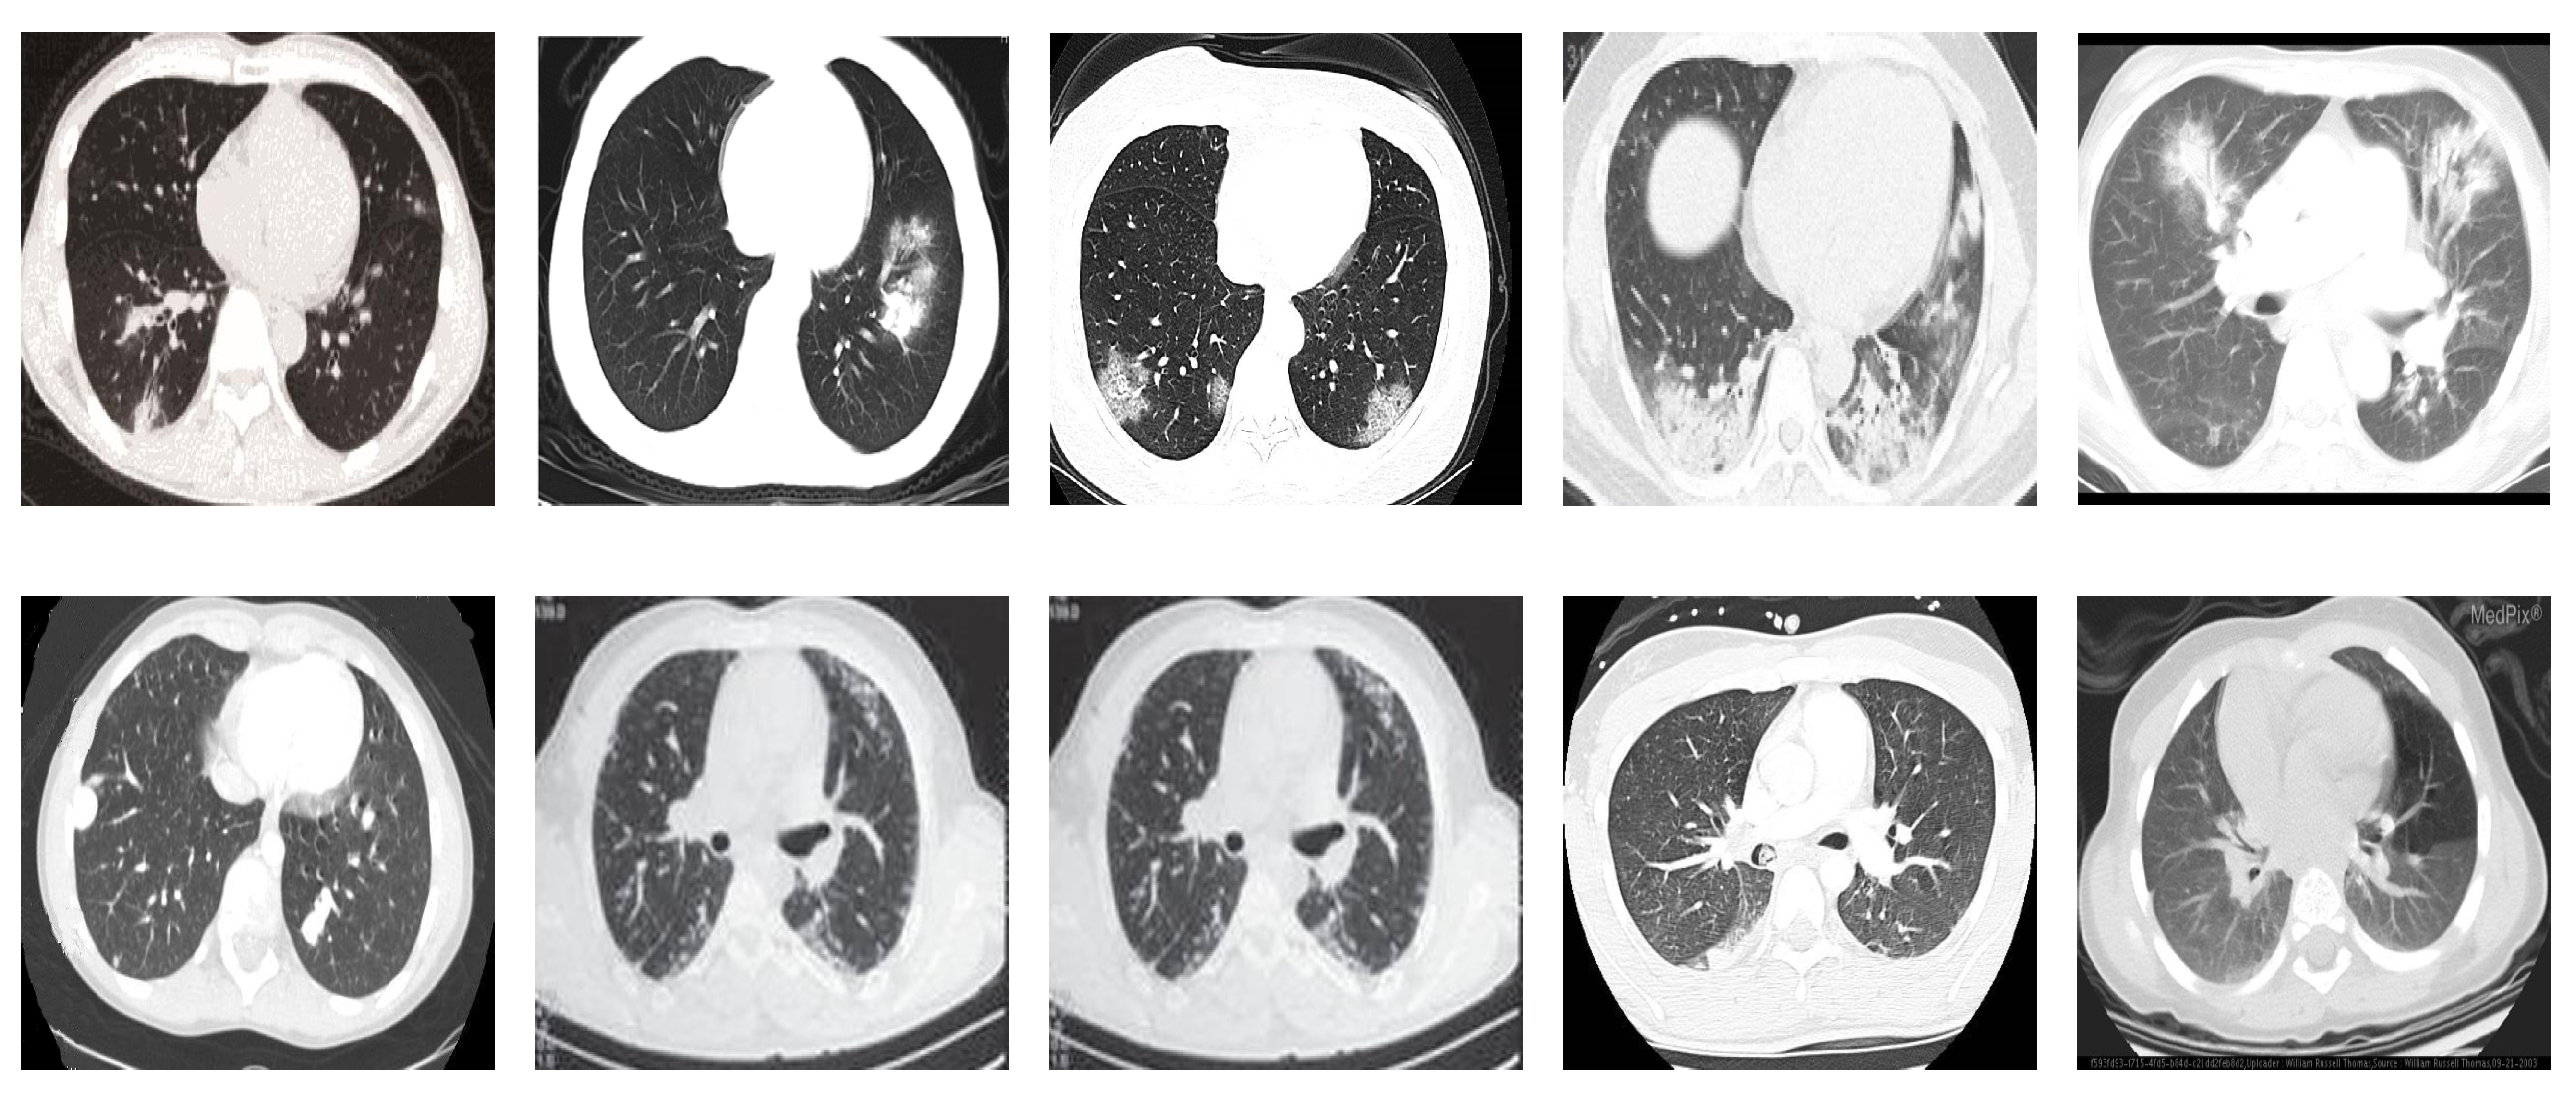

COVID19-CT dataset [54]: The dataset consists totally of 746 CT images. There are 349 CT images of patients with COVID-19 and 397 CT images showing non-COVID-19, but other pulmonary diseases. The positive CT images were collected from preprints about COVID-19 on medRxiv and bioRxiv, and they feature various manifestations of COVID-19. Since the CT images were taken from different sources, they have varying sizes between and . Figure 8 shows example CT images from the COVID19-CT dataset.

Figure 8.

Examples of chest CT images from the COVID19-CT dataset. The first row represents CT images diagnosed with COVID-19, whereas the second row represents non-COVID-19 cases, but other lung diseases.

On the COVID19-CT dataset, the overall performance with respect to all evaluation metrics is inferior to that on the SARS-CoV-2 dataset. This can be attributed to the cross-source heterogeneity of the CT images in the dataset. The non-COVID-19 CT images were taken from different sources and show diverse findings which pose difficulty to distinguish between COVID-19 and other findings associated with lung diseases due to the potential overlap of visual manifestations (see Figure 8). Another reason is that the CT images in the COVID19-CT dataset show strong variations in contrast, variable spatial resolution, and other visual characteristics which could affect the model’s ability to extract more discriminative and generalizable features.